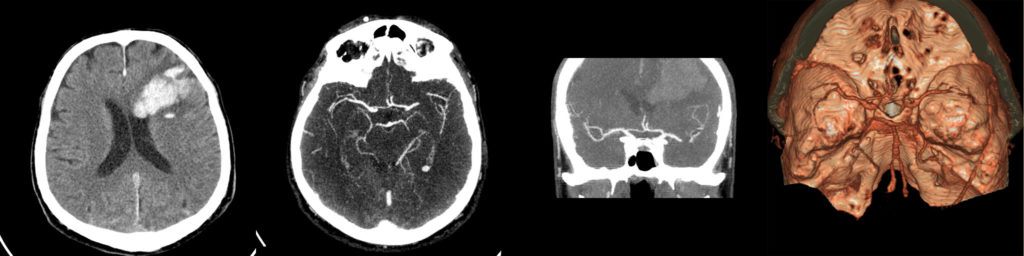

Angiografia CT

Aplicabilitate:

- evaluarea structurilor vasculare;

- evaluarea afecțiunilor neurovasculare;

- caracterizarea anevrismelor, stenozelor și anomaliilor vasculare;

- analiza vasculaturii capului și a gâtului, incluzând arcul aortic și emergențele arterelor cervicale;

- planificarea tratamentului intervențional.exclude cauzele care mimează AVC;

- indică prezența ocluziei, gradul și localizarea acesteia;

- precizează extensia trombului (poate fi cuantificată prin măsurarea lungimii acestuia în arborele arterial. Extinderea intracranială a trombului prezice evoluția clinică, mărimea finală a infarctului și transformarea hemoragică)

- evidențiază circulația colaterală și starea parenchimului cerebral;

- exclude disecția arterială cranio-cervicală;

- evidențiază și evaluează stenozele vasculare;

- poate face diferențierea între un tromb ocluziv total, subocluziv sau stenoză aterosclerotică – patologie trombo-stenotică.

Pentru evaluarea pacienților cu AVC acut, angiografia CT este o metodă rapidă și acurată, informațiile relevante în ceea ce privește atât calibrul și permeabilitatea vasculară, cât și perfuzia parenchimatoasă fiind obținute la prima trecere a substanței de contrast aplicată în bolus.

Evidențierea imagistică completă a arborelui arterial de la arcul aortic până la vertex în evaluarea atât a ocluziilor acute, cât si a stenozelor cronice poate fi realizată în timpul încărcării maxime cu contrast (peak).